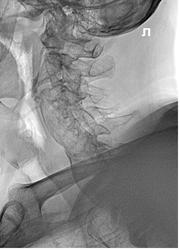

Порерыв литературу настолько быстро, насколько это позволял режим работы "на потоке"в  рентгеновском кабинете  в скоропомощой больнице и посоветовавшись с рентгенологами кабинета КТ, и нейрохирургами, так и не нашлось убедтиельной версии. Наиболее близко это к болезни Форестье? Смущает масштаб поражения и отсутствие замыкательных пластин, а так же остеопороз.

Перелом описала в суставных отростках С7. На КТ перелом правой дужки и поперечного отростка С7 со смещением отломков.

Форестье. Но суть не в этом. Непонятно, что с суставными парами С6-7... Такое расхождение остистых С6 и С7, кортикал заднего края С6 в проекции костного канала спинного мозга. У меня впечатление перелома и С6, и С7 с травматическим вывихом в суставной паре С6-7 минимум...

Нужны дайкомы, или хотя бы сагитталы по суставным отросткам справа и слева (детализация соотношений в суставах и целостности суставных отростков), штуки по 3 реконструкций, + короналы зоны интереса. Перелом остистого не увидела: на сагиттале часть заднего края отростка "в срезе", скорее всего.

Перелом я описывала в суставных, а на КТ он оказался в дужке и в поперечном отростке С7 справа. С6 повреждение не описывалось. Хотя мне очень интересно почему идет такое прерывание тени передней продольной связки на уровне тела С6? это компонент перелома?  там есть аутогаз, но и травма 2 недели назад.

К сожалению не достать мне дайкомы. Может на следющей неделе достану только. Для меня было интереснее Форестье это или нет. Были по рентген- снимкам версии и  тбк спондилита и конкресценции.

Грудной еще посмотрите начинается то с него чаще Форестье.